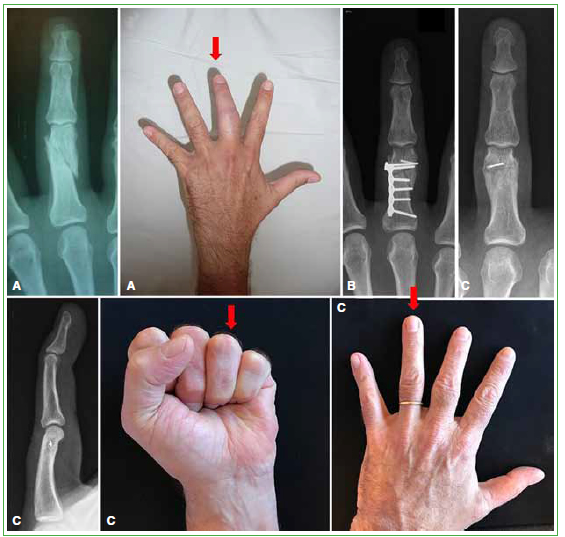

El seguimiento objetivo (movilidad, EAV y DASH) promedio desde la osteotomía fue de 34 meses (rango 6-62) (Figura). Tres pacientes se negaron o no pudieron concurrir a un nuevo control presencial, por lo que solo se pudo actualizar su evaluación subjetiva (DASH y EAV) por correo electrónico y se tuvieron en cuenta los últimos registros de movilidad que figuraban en la historia clínica. En 12 casos, la falange involucrada fue la primera y, en un caso, la segunda. La indicación de osteotomía fue por deformidad en varo-valgo (6 falanges), por deformidad articular (4 falanges) y por defectos rotacionales (3 falanges).

Figura. A.

Radiografía e imagen clínica de una consolidación viciosa combinada de dos meses de evolución. B. Radiografía posoperatoria. C. Resultado a los 62 meses del retiro de la osteosíntesis y una tenólisis asociada por adherencias. Se puede observar el remanente de una mecha en la falange, que no ocasionó molestias.